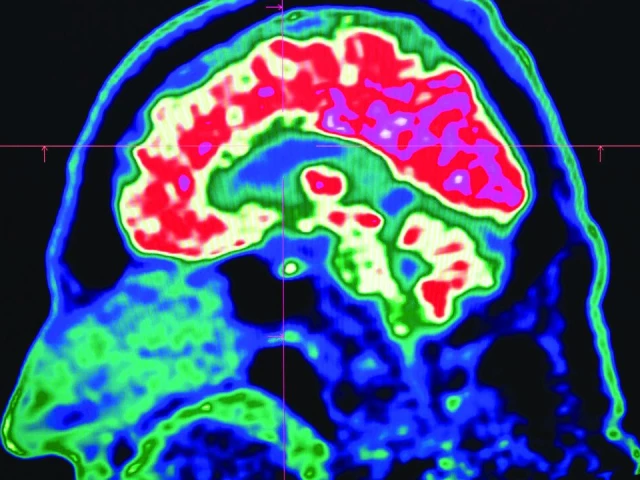

Tiny shards of plastic called microplastics have been detected accumulating in human brains, but there is not yet enough evidence to say whether this is doing us harm, experts have said.

As reported by AFP, these mostly invisible pieces of plastic have been found everywhere from the top of mountains to the bottom of oceans, in the air we breathe and the food we eat. They have also been discovered riddled throughout human bodies, inside lungs, hearts, placentas and even crossing the blood-brain barrier.

The most prominent study looking at microplastics in brains was published in the journal Nature Medicine in February.

The scientists tested brain tissue from 28 people who died in 2016 and 24 who died last year in the US state of New Mexico, finding that the amount of microplastics in the samples increased over time.

The study made headlines around the world when the lead researcher, US toxicologist Matthew Campen, told the media that they detected the equivalent of a plastic spoon’s worth of microplastics in the brains.

Campen also told Nature that he estimated the researchers could isolate around 10 grammes of plastic from a donated human brain — comparing that amount to an unused crayon.